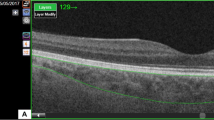

Measurement of CVI

The CVI was measured using established methods with minor modifications4,24. EDI—OCT images that traversed the fovea were selected for analysis. Image binarization and segmentation were performed using the ImageJ software, version 1.47 (Bethesda, MD, USA; http://imagej.nih.gov/ij/). The total choroidal area (TCA) was determined as the chosen region within the subfoveal choroid, spanning a width of 1500 μm (with 750 μm extending both nasally and temporally from the fovea). The vascular LA was defined as the area occupied by dark pixels, whereas the SA was defined as the area occupied by light pixels. The CVI was defined as the ratio of LA to TCA (Fig. 1).